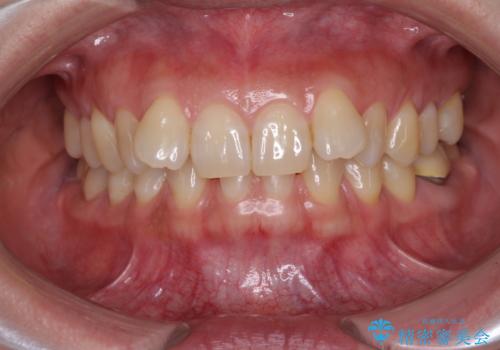

下顎2前歯の欠損 インビザラインによる抜歯矯正

- 下顎前歯欠損による歯列不正を気にして来院された患者様です。

下顎の歯列が小さく、下顎前歯が隠れてしまう過蓋咬合(ディープバイト)であったため、

マウスピースでの抜歯矯正特有の抜歯スペースに向かって奥歯が傾斜する動きが顕著に表れ、ディープバイトは改善されませんでした。

前歯のみが強く接触し、奥歯で咬めない期間も続いたため、ワイヤー装置などを補助的に使用し、何とか終了させることができました。